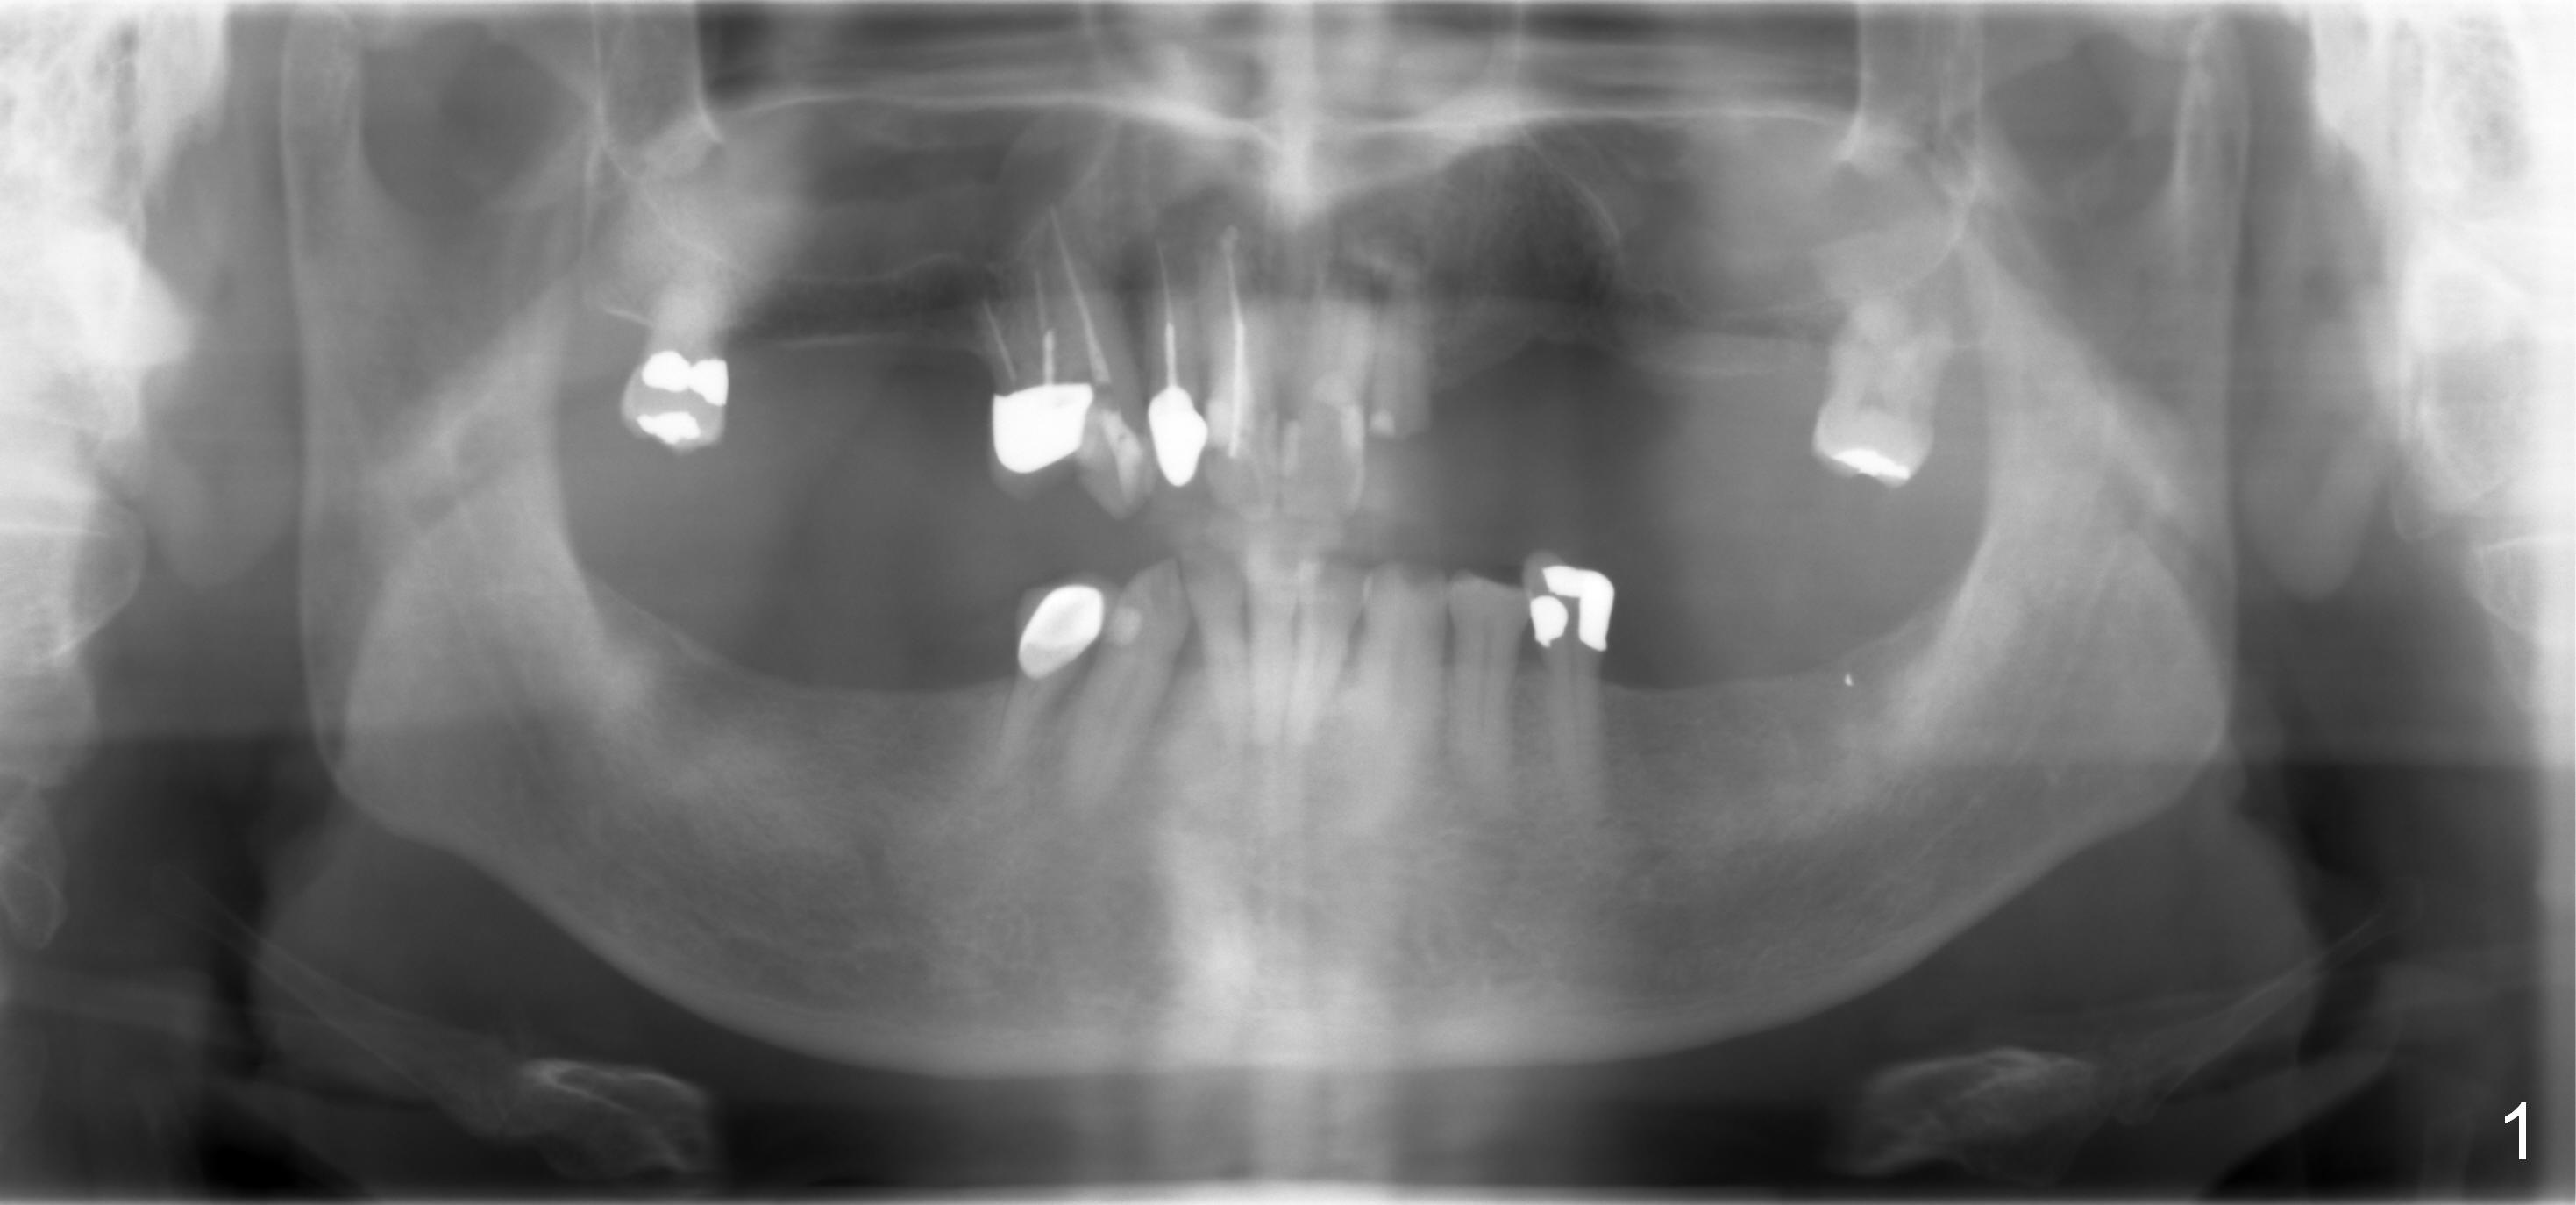

A 70-year-old man (TF) requests implant restoration for the upper left quadrant first (Fig.1), exactly #10 and 11 first (Fig.2-4). There is periapical radiolucency associated with the residual root at #10 (Fig.2 *). Local antibiotic will be Metronidazole. The root of #10 is long and large. The bone at #11 looks loose. Long implants will be placed (Fig.4). Osteotomy preparation should be less.